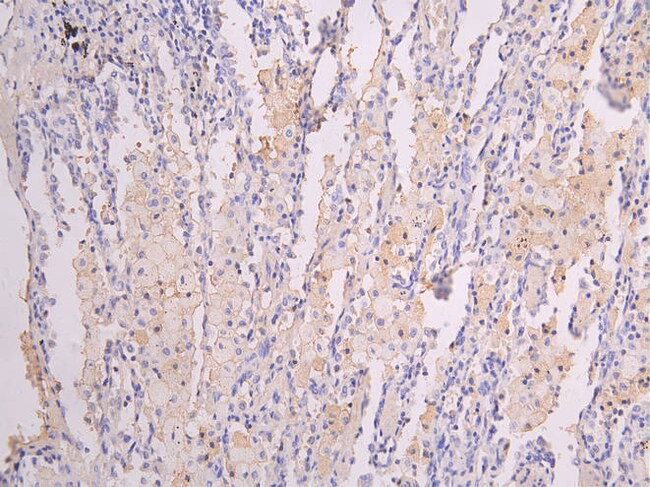

ICAM-1 Recombinant Monoclonal Antibody for Western Blot, IHC (P), Flow, ELISA

ICAM-1 (CD54) is an 85-110 kDa single-chain type 1 integral membrane glycoprotein with an extracellular domain of five immunoglobulin superfamily repeats, a transmembrane region and a cytoplasmic domain. ICAM-1 has 7 potential N-linked glycosylation sites and shares considerable amino acid sequence homology with ICAM-3 (CD50) and ICAM-2 (CD102). ICAM-1 binds to integrins of type CD11a/CD18 (leukocyte adhesion molecule, LFA-1), or CD11b/CD18 (Mac-1) and is exploited by Rhinovirus as a receptor. ICAM-1 is expressed by activated endothelial cells and detected on epithelial cells, fibroblasts, chondrocytes, B lymphocytes, T lymphocytes (low), monocytes, macrophages, dendritic cells and neutrophils, with lower levels that increase upon inflammation. ICAM-1 is also detected in some carcinoma and melanoma cells. Soluble ICAM-1 is detectable in the plasma and is elevated in patients with various inflammatory syndromes.

| ELISA, Flow Cytometry, Immunohistochemistry (Paraffin), Western Blot | |